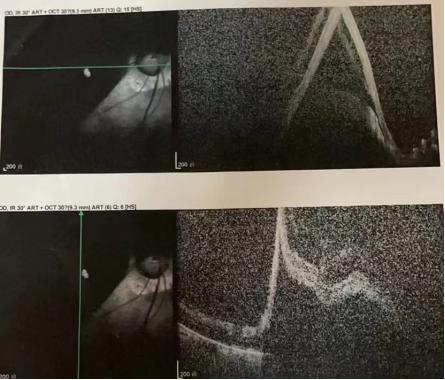

患者右眼术前眼底照相

患者术前OCT

术后第一天眼底照相

术后第一天OCT